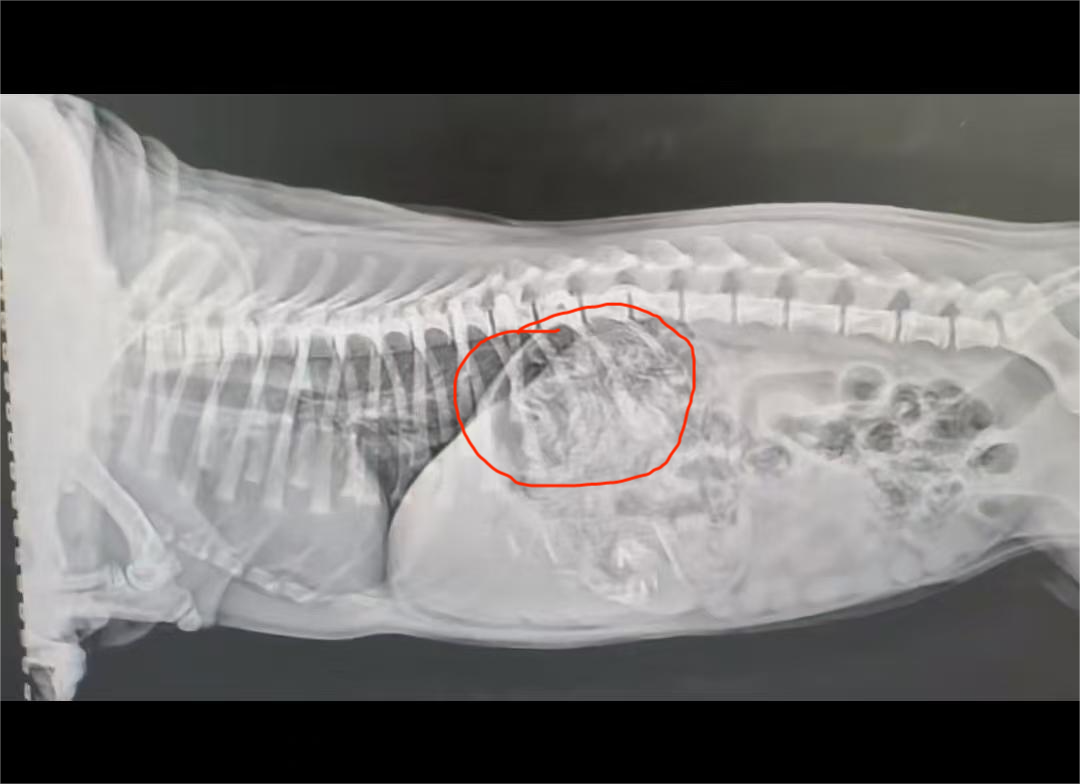

The veterinary team first used X-ray imaging to locate the foreign object. The dog was then placed under general anesthesia.

- X-ray or ultrasound to confirm foreign body location